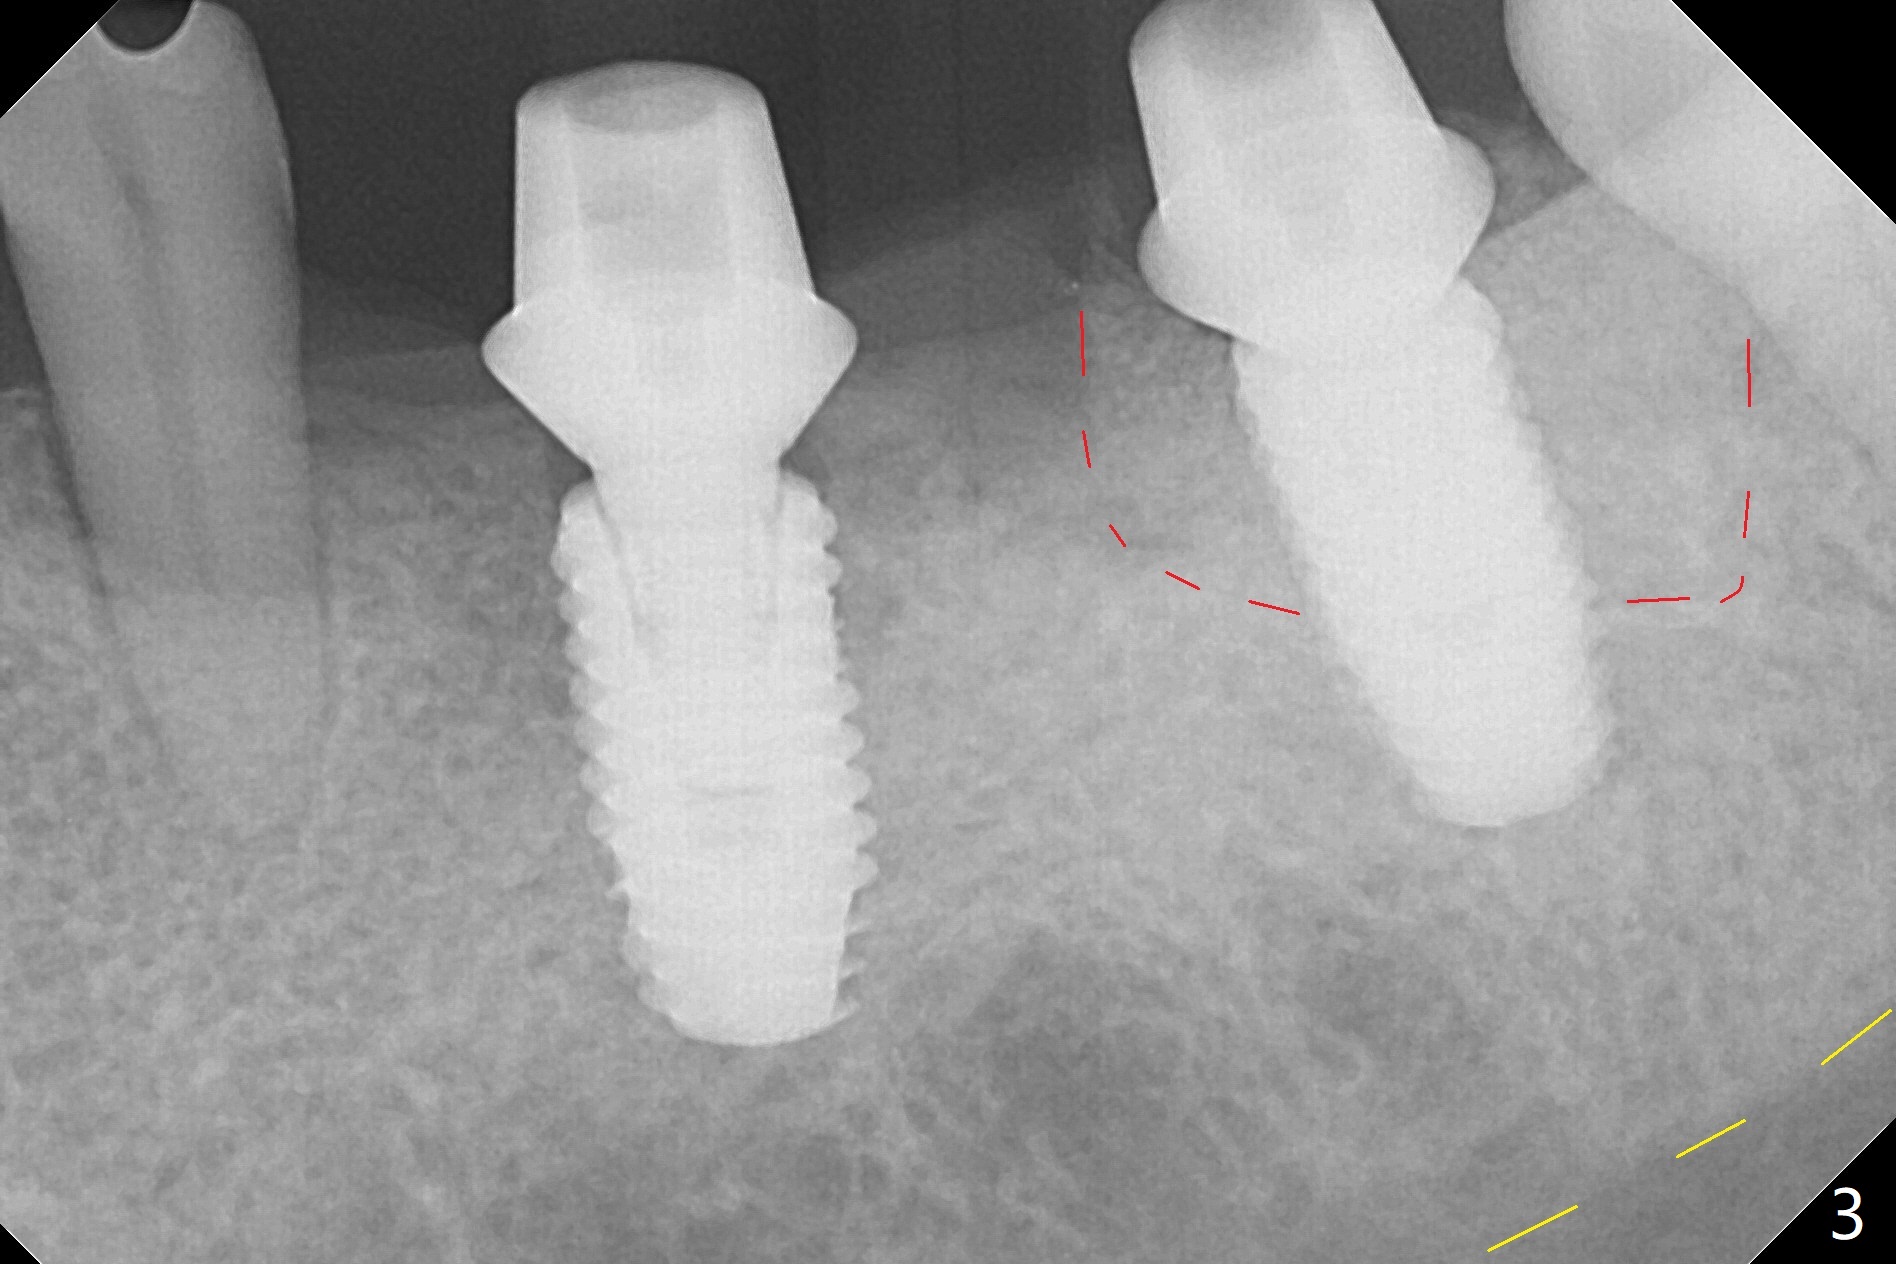

Re-analysis of preop CT reveals extensive bone loss around #18 (Fig.1 (lingual view)). Blood is withdrawn for sticky bone. After implant placement (Fig.2), sticky bone is placed at #18 (Fig.3 red dashed line (yellow: superior border of the Inferior Alveolar Canal)). PRF membrane and an immediate provisional FPD (#18-20) further keep the bone graft in place for healing. Four months postop, the patient reports difficulty in mastication on the left and requests extraction of the tooth #20 for implant (Fig.4). The implant will be placed lingually, while socket shield will be performed buccally (Fig.5 S) to keep bone graft in place. The implant at #19 is equicrestal (Fig.6); the one at #18 is apparently supracrestal buccally (Fig.7). Since there is a lot of scattering from nearby crowns, the implant at #20 will be placed free hand. To overcome the thick dense lingual plate (Fig.8 L), osteotomy is initiated (Fig.9 red line) in the middle of the lingual wall of the extraction socket (black area) on the top of the socket shield (S). After the last drill (3.5x11.5 mm, Fig.10 pink) and before 4x11.5 mm implant, use Lindamann bur to remove the coronal portion of the lingual plate (Fig.11 red line) to prevent implant buccal deviation.